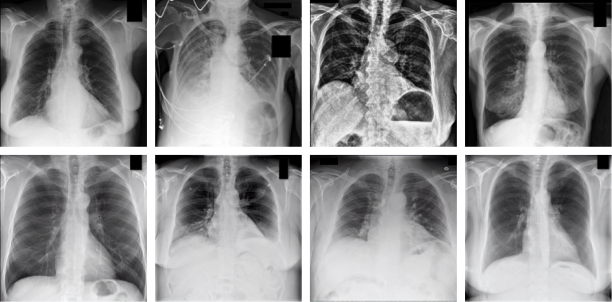

Figure 1: The first row displays real X-ray images, while the second row shows generated images. The diagnostic classifications of the real images are: Normal, Pleural Effusion, Atelectasis, and Hyperinflated Lungs. Black boxes are used for anonymization.

To generate synthetic chest X-rays, RoentGen, an LDM-based generative model, is used [42]. A noisy image vector is conditionally denoised by a U-Net based on the text embedding generated by the encoder. The variational autoencoder then decodes the latent vector and maps it to a pixel space, which results in a high-resolution generated image. Patient reports from the MIMIC-CXR dataset were utilized to conditionally create chest X-rays [43]. Each report corresponds to a real chest X-ray image from an imaging study. To avoid unintentional loss of information, selected reports must meet RoentGen’s token length limit. These reports were then processed through RoentGen, producing synthetic chest X-ray images at a resolution of 512x512 with 75 inference steps.

3.2.2 Real Stimuli

The MIMIC-CXR dataset contains 227,835 imaging studies with 30 reports being randomly selected from this set. As each synthetic chest X-ray was generated from a report in the MIMIC-CXR dataset, each synthetic chest X-ray has a corresponding real X-ray with the same report content. These corresponding X-rays were the ones selected to be used in the study.